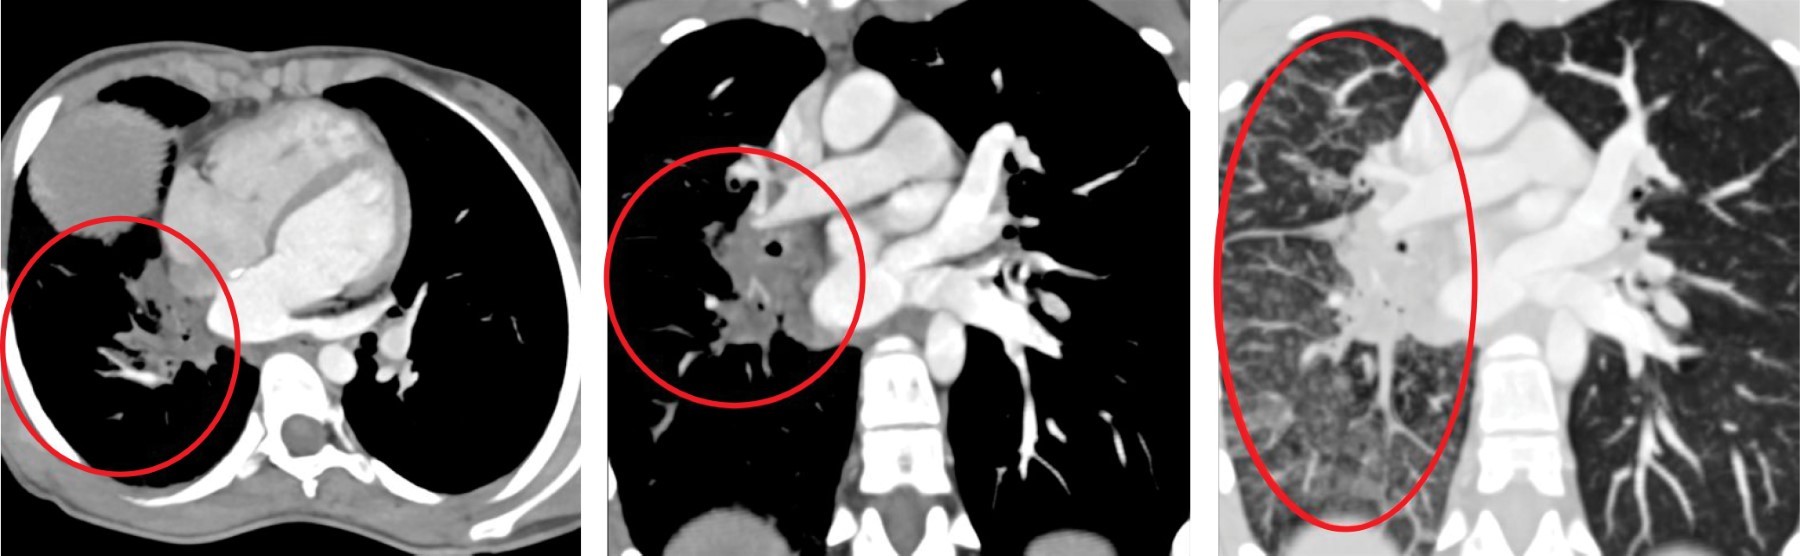

A 12-year-old female with a history of non-obstructed TAPVC to the coronary sinus underwent total correction at nine months of age. At one year of age, an echocardiogram with color flow Doppler (Figures 1 and 2) documented obstruction of the right PV with a mean gradient of 13 mmHg. Subsequently, a contrast-enhanced computed tomography angiography (angioTAC) was requested (Figure 3), which reported drainage of PV with patent flow. No collector was identified, but three PV were observed, two on the left and one on the right. In the lower left and right PV, a small hypodense band was noted, a finding suggestive of a partial septum at each origin. Reported diameters were as follows: superior right PV of 3.4 mm, superior left PV of 3.2 mm, and inferior left PV of 3.4 mm. The patient showed appropriate evolution and was lost to follow-up.

Figure 3